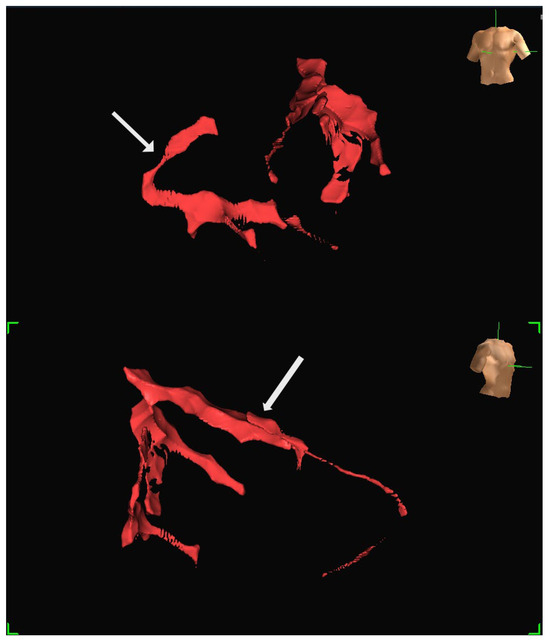

The Role of Imaging in Ventricular Tachycardia Ablation

by Pasquale Notarstefano, Michele Ciabatti, Carmine Marallo, Mirco Lazzeri, Aureliano Fraticelli, Valentina Tavanti, Giulio Zucchelli, Angelica La Camera and Leonardo Bolognese

Ventricular tachycardia (VT) remains a major cause of morbidity and mortality in patients with structural heart disease. While catheter ablation has become a cornerstone in VT management, recurrence rates remain substantial due to limitations in electroanatomic mapping (EAM), particularly in cases of deep [...] Read more.

Ventricular tachycardia (VT) remains a major cause of morbidity and mortality in patients with structural heart disease. While catheter ablation has become a cornerstone in VT management, recurrence rates remain substantial due to limitations in electroanatomic mapping (EAM), particularly in cases of deep or heterogeneous arrhythmogenic substrates. Cardiac imaging, especially when multimodal and integrated with mapping systems, has emerged as a critical adjunct to enhance procedural efficacy, safety, and individualized strategy. This comprehensive review explores the evolving role of various imaging modalities, including echocardiography, cardiac magnetic resonance (CMR), computed tomography (CT), positron emission tomography (PET), and intracardiac echocardiography (ICE), in the preprocedural and intraprocedural phases of VT ablation. We highlight their respective strengths in substrate identification, anatomical delineation, and real-time guidance. While limitations persist, including costs, availability, artifacts in device carriers, and lack of standardization, future advances are likely to redefine procedural workflows. Full article